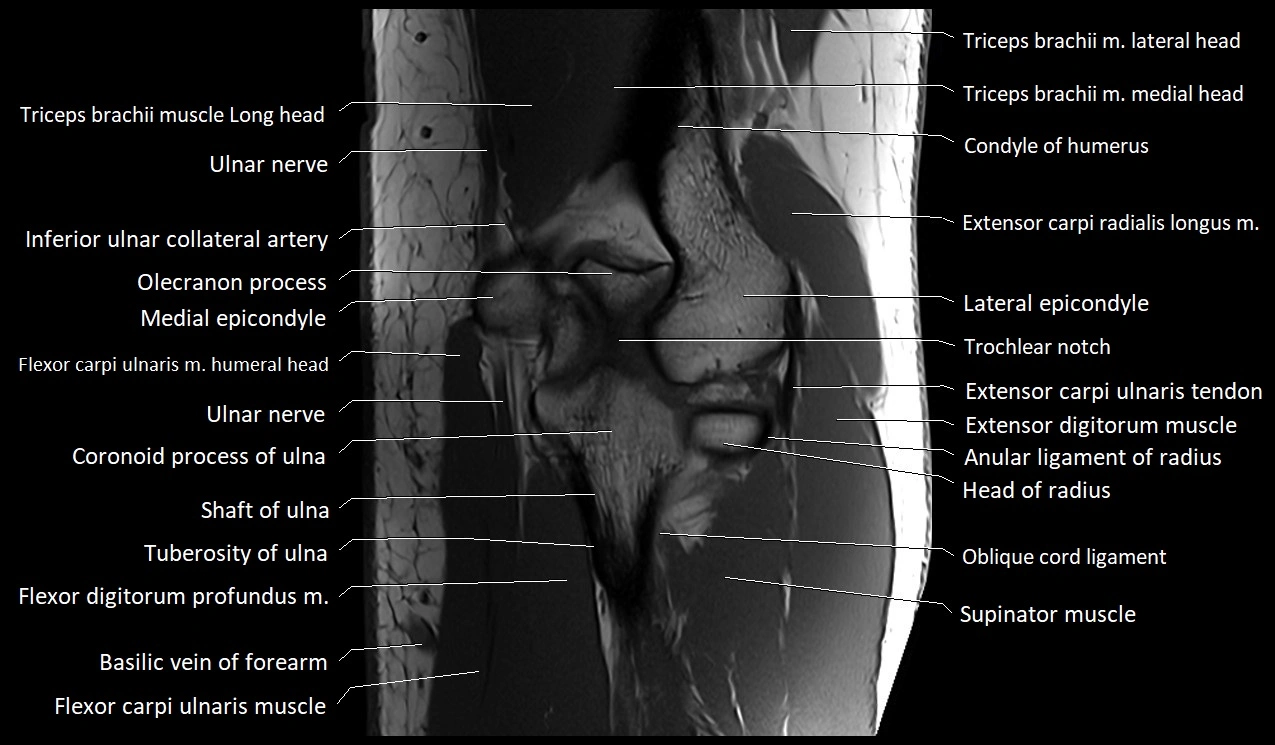

MRI image

image